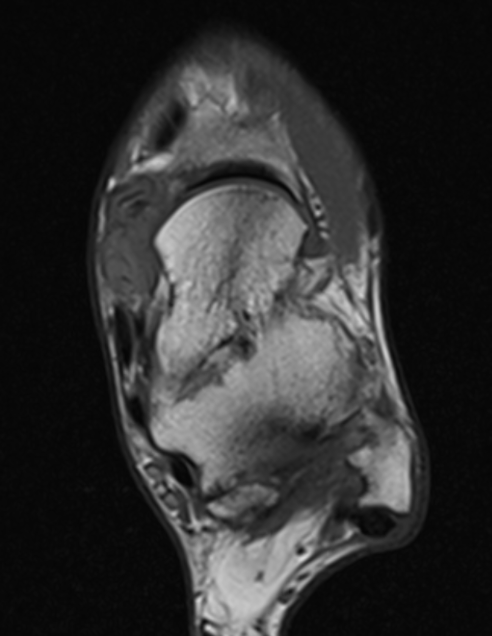

GCT flexor tendon sheath

GCT of tibialis posterior tendon sheath